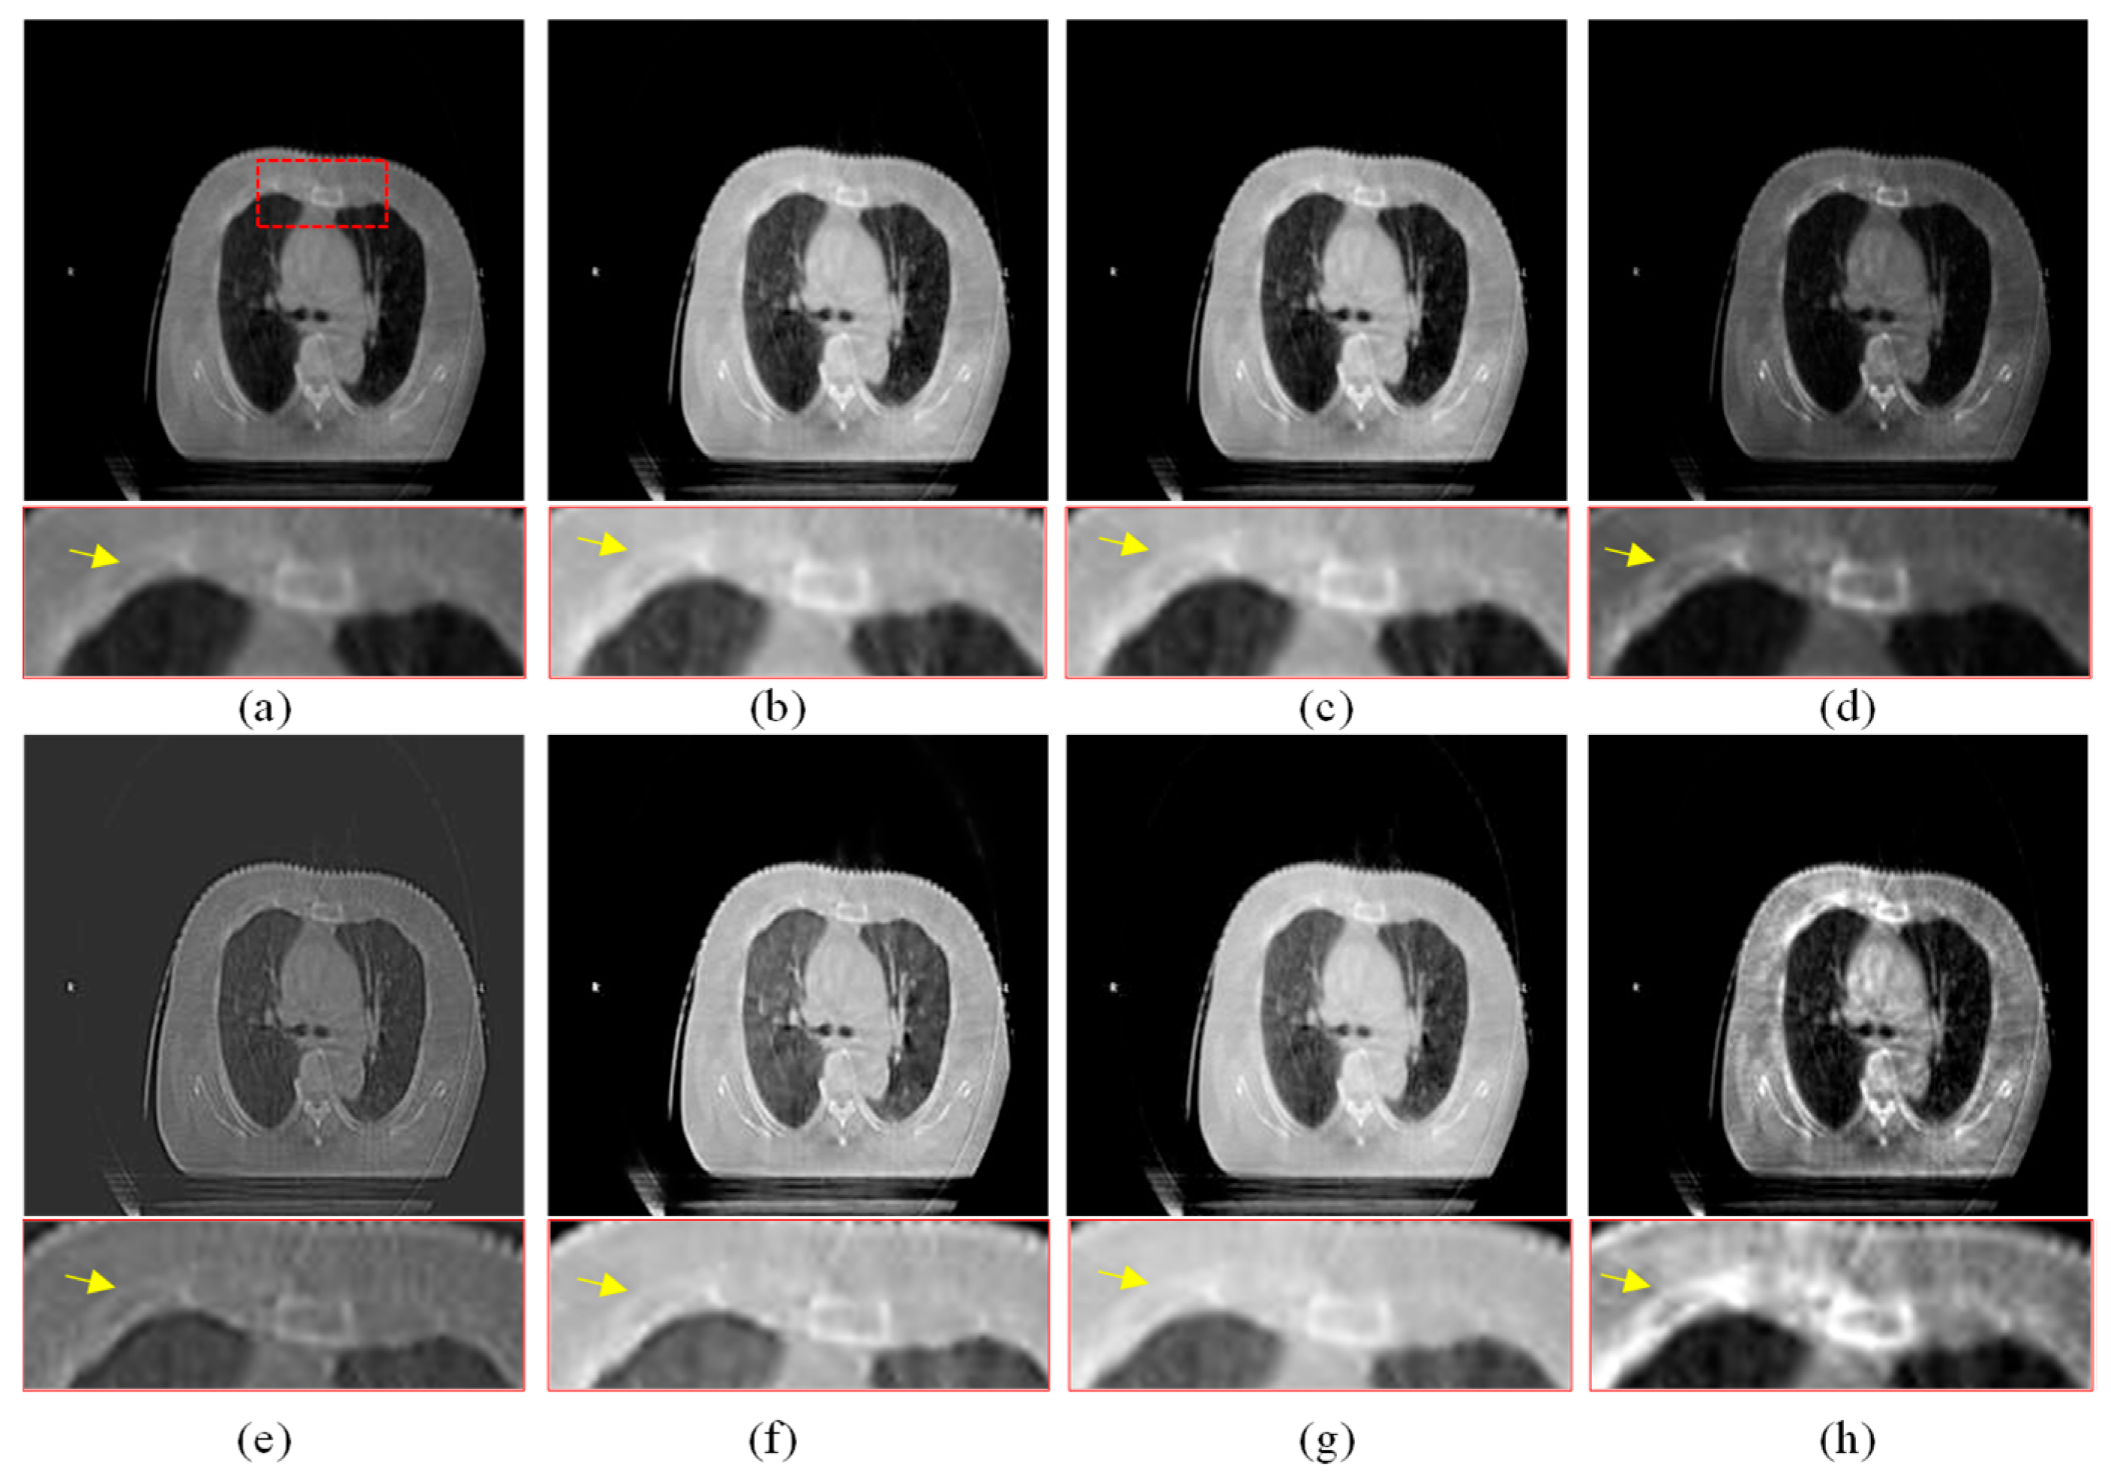

Another three sets of experiments are shown in Figure 8, Figure 9 and Figure 10. As can be seen from the enlarged regions and the yellow arrows in Figure 8, it is difficult to directly observe the presence of skeletal information at this position from the enlarged region in Figure 8a. The enhancement results of the comparison methods also did not improve the visual contrast in this region, but the skeletal information can be clearly observed in our result, which means our results outperform the comparison algorithms in terms of detail, contrast, and visualization effect.

The same conclusion can also be obtained in Figure 9 and Figure 10. Especially in the enalrged region in Figure 10, our results provide a much clearer organizational structural and edge infromation, which is very helpful for disease diagnosis and treatment. Through comparison, it can be found that the rigidity informaiton in our results is more significant, the tissue edge in our results is clearer, and the contrast of the texture structure is also better than that of the comparison algorithms. The observation effect is greatly improved by our enhancement method, proving that our method can effectively enhance the CBCT images.

In this section, the registration results between the source CBCT and CT images and between the CBCT images enhanced using different enhanced algorithms and CT images are compared and analyzed. In this experiment, all the registration results are obtained by the same registration model [39]. In addition to visual analysis, we also give the SSIM values before and after the registration of these images to objectively measure the registration performance.

As shown in Figure 12, Figure 12a is the unregistered source CBCT and CT images. The SSIM value of the source images is 0.5532, and it can be seen from Figure 12a that the imaging position and size of the source CBCT and CT images are different. Figure 11b is the registration result by the source CBCT and CT, and the SSIM value is 0.7184 if the CBCT image is used directly for the registration task. In the enlarged image, the edge regions are not exactly aligned in Figure 12b. Except for the CBF enhancement method, the registration accuracy was improved after CBCT images were enhanced by other methods. For example, in Figure 12c, the SSIM value is 0.7486 by registering the MSR-enhanced CBCT and CT images, which shows improved accuracy of non-enhanced CBCT and CT registration. In other words, the enhancement of CBCT images is helpful to improve the registration accuracy of CBCT and CT, which is very critical and meaningful for IGRT.

Figure 12.

Registration comparison. The positions of the two images are shown in different colors. (a) Source CBCT and CT images. (b) Registration results of source CBCT and CT images. (c) Registration results of MSR-enhanced CBCT and CT. (d) Registration results of MSRCR-enhanced CBCT and CT. (e) Registration results of DCP-enhanced CBCT and CT. (f) Registration results of CBF-enhanced CBCT and CT. (g) Registration results of RRM-enhanced CBCT and CT. (h) Registration results of SMIPC-enhanced CBCT and CT. (i) Registration results of CBCT and CT enhanced by our method.

From the yellow arrows, it can be seen that our method’s results have the highest registration accuracy and achieve the best SSIM value of 0.7729. In the enlarged image, it can be seen that the proposed method outperforms the comparison methods in the registration accuracy of the edge regions. This is because the proposed method enhances the saliency features, which plays a key role in the registration process. In addition, since the proposed method includes the denoising step, the noise points on the edges of image that may affect the registration were filtered out, which also helps to improve the registration accuracy.